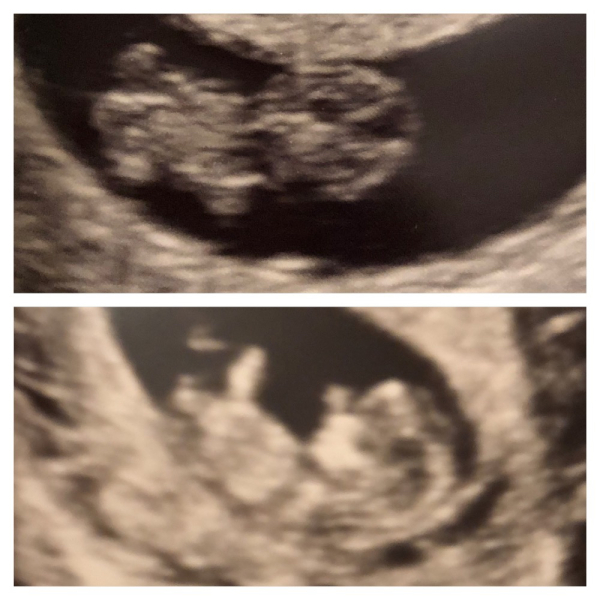

My 10 week scan last time was amazing, it's incredible just how much growth happens between 8&10 weeks. I'll see if I can attach pictures. Might help you decide when to book in for.

squirrelnutkins1 · 04/12/2022 14:02

8 and 10 weeks

@squirrelnutkins1, aww they're cute! I couldn't believe the difference between 6-9 and 9-12 weeks! Unfortunately we didn't get a 9 week picture as EPAU had just bought an ultrasound machine (great idea as otherwise you had to be scanned in the main department with all the other pregnant ladies). Since it was brand new - we were the very first couple to scanned - it wasn't hooked up to a printer at that point. It's just incredibly at how quickly they grow and the different in just a few weeks is unbelievable! 🥰

@squirrelnutkins1 proper little baby by 10 weeks🥺